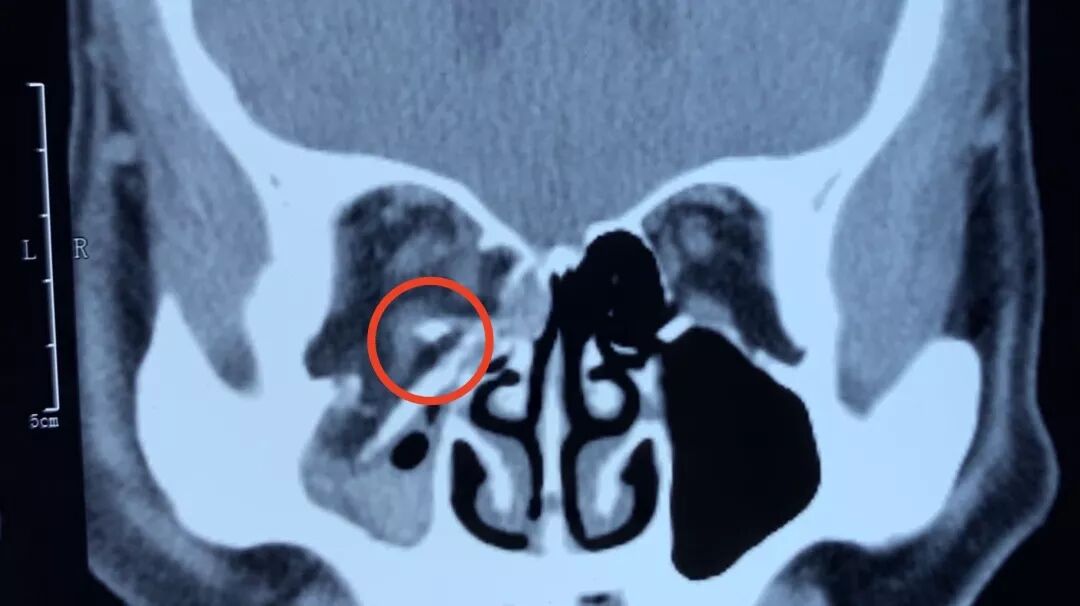

肖主任介绍说,爆裂性骨折,复视,眼球运动障碍和眼球凹陷是主要症状和体征。复视程度与骨折部位及范围大小有关。眶底骨折多出现垂直位复视,常主诉下楼梯或阅读困难,眶内壁骨折多出现水平位复视。通过眼眶CT可以一目了然的了解有无骨折及其部位,范围,有无软组织或肌肉嵌顿等。

上图可见眼眶内侧壁和下壁骨折,眼眶内容物进入鼻腔